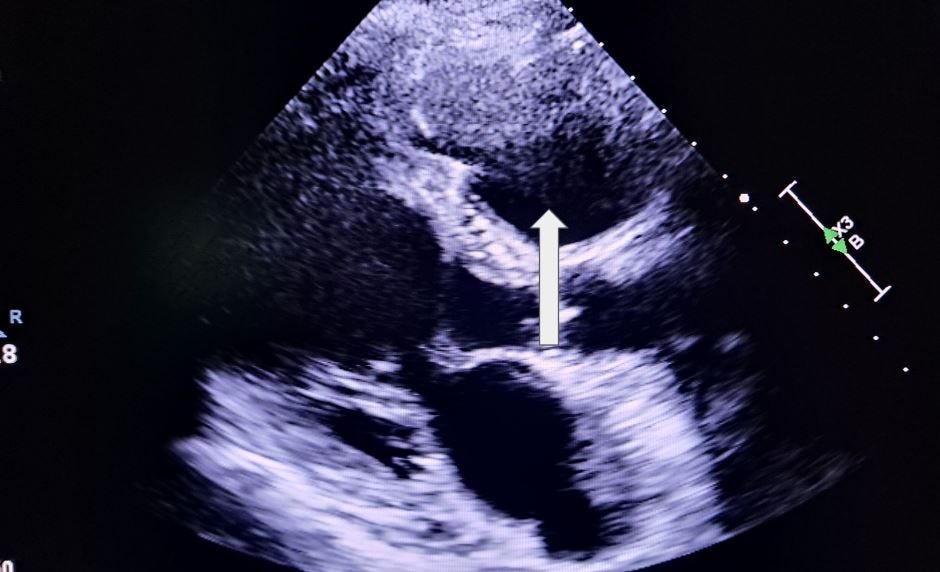

Which chamber is displayed on this parasternal long axis image?

A. Right atrium

B. Left atrium

C. Left ventricle

D. Right ventricle